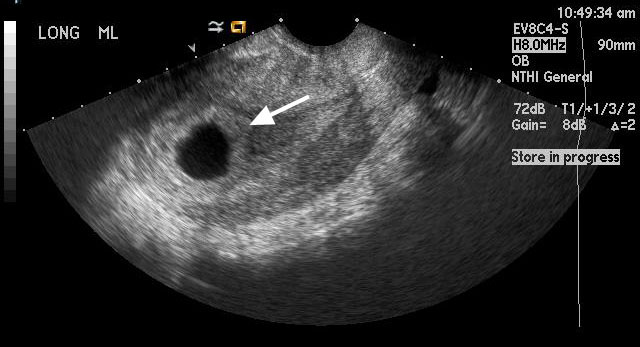

Figure 2

This image shows left adnexal ectopic pregnancy with the arrow pointing towards the anechoic gestational sac, which is separate from the left ovary (arrowhead). |

|

For comparison, this image shows a normal intrauterine pregnancy at 6 weeks gestation. The arrow points to an anechoic fluid filled gestational sac within the uterus. You can note the decidual reaction which is the hyperechoic area surrounding the gestational sac. |